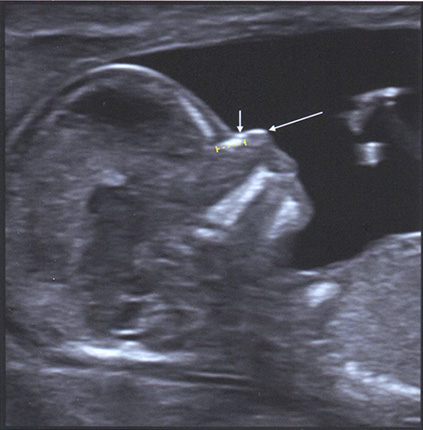

У большинства плодов с трисомией 21 или другими анеуплоидиями в ранние сроки носовые кости гипоплазированы или не оссифицированы (рис. 1.3). В норме в I триместре беременности хотя бы одна из двух носовых костей визуализируется в сагиттальном сечении. Следует отметить, что ультразвуковая оценка носовых костей технически сложна и требует от специалиста определенных навыков. Было доказано, что правильное выведение ультразвукового изображения носовых костей улучшает результативность комбинированного скрининга на синдром Дауна. Иногда в сроке 11 нед и в начале 12-й недели беременности носовые кости отсутствуют или кажутся недостаточно оссифицированными. В этом случае рекомендуется повторить ультразвуковое исследование через неделю. В табл. 1.2 приведены основные критерии правильной оценки носовых костей в I триместре беременности.

Рис. 1.3. Среднесагиттальный срез головы плода в 13 нед беременности, демонстрирующий нормальное изображение носовой кости (НК), согласно стандартам, описанным в табл. 1.2. Желтые калиперы измеряют НК. Обратите внимание на наличие двух других структур помимо НК: верхняя линия, параллельная НК, - кожа носа (короткая стрелка).